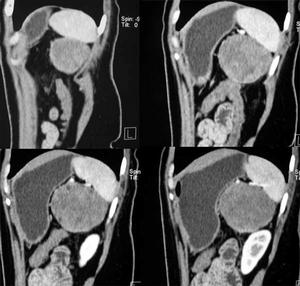

7、保留子宮者,為明確有無葡萄胎組織侵入肌層,可作超聲檢查、子宮碘油造影及盆腔動脈造影。

3.超聲檢查B型超聲為非侵入性檢查,可以早期發現葡萄胎組織侵入子宮肌層程度,協助診斷子宮內滋養細胞腫瘤病灶。宮壁顯示局灶性或瀰漫性強光點或光團與暗區相間的蜂窩樣病灶,應考慮為侵蝕性葡萄胎或絨癌。